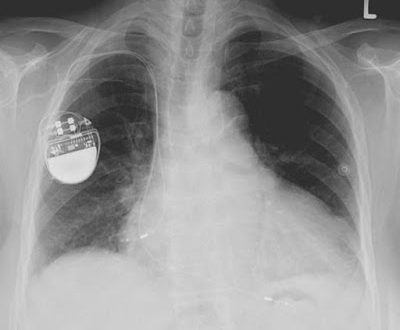

Από τα στοιχεία που συνέλεξαν οι δύο εισαγγελείς προκύπτει πως οι δύο εταιρίες που προμήθευαν δύο δημόσια νοσοκομεία, στις χρήσεις αντίστοιχα από 2005 έως 2009 και 2006 έως και 2007, εμφανίζονται να πραγματοποίησαν αγορές εμπορευμάτων από συνδεδεμένες εταιρίες με έδρα την Κύπρο. Εικάζεται πως αυτές είχαν δημιουργηθεί αποκλειστικά και μόνο για την αύξηση του κόστους αγορών με σκοπό να “ανεβαίνει” η τιμή των υλικών -όπως βηματοδότες κ.α. Από την εισαγγελική έρευνα προκύπτει πως οι επίμαχες αγορές από την Κύπρο ήταν ψευδείς, αφού η κάθε μια από τις εν λόγω ελληνικές εταιρίες είχε αγοράσει τα πωλούμενα ιατρικά είδη απευθείας από την κατασκευάστρια και όχι τη συνδεδεμένη εταιρία σε τιμές υποπολλαπλάσια χαμηλότερες εκείνων που αναγράφονταν στα τιμολόγια.

Κατά τους εισαγγελείς, οι επίμαχες συναλλαγές με τις κυπριακές εταιρίες σχεδόν στο σύνολο τους ήταν τριγωνικές με αποτέλεσμα η μία εταιρία να έχει καταβάλει μεγαλύτερο τίμημα για αγορές, κατά το διάστημα 2005 έως και 2009, συνολικά 19,9 εκατομμύρια ευρώ, ενώ η δεύτερη εταιρία, στις χρήσεις 2006 και 2007 κατέβαλε ποσά για προμήθειες εμπορευμάτων συνολικά 53,5 εκατομμύρια ευρώ. Επίσης τα εμπορεύματα φαίνονται να έφθαναν από τους κατασκευαστές στις εγχώριες εγκαταστάσεις των εταιριών με δελτία αποστολής και στη συνέχεια να εκδίδονταν τιμολόγια από τις αλλοδαπές εταιρίες.